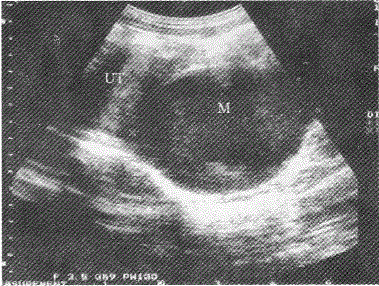

女性,15岁,周期性下腹部疼痛伴排尿困难;月经未来潮;超声检查如图所示,最可能的诊断为

A

宫颈下方阴道内见无回声暗区,边界清晰,无回声区内有细小点状回声,结合症状。